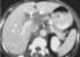

Calcified lymph nodes at porta hepatis

Lymphadenopathy or adenopathy is a disease of the lymph nodes, in which they are abnormal in size or consistency. Lymphadenopathy of an inflammatory type (the most common type) is lymphadenitis, producing swollen or enlarged lymph nodes. [Source: Wikipedia ]